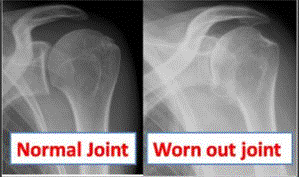

Arthritis or degenerative joint disease of the shoulder occurs when the cartilage gets worn away.  The joint develops spurs and the surface becomes irregular. In the end all the cartilage is gone and the two bones in the joint rub against each other causing debilitating pain and stiffness.

Shoulder arthritis can be due to wear and tear and be part of a generalised arthritis in the hips and knees; this is called primary arthritis. Rheumatoid arthritis is a common cause or an injury to the shoulder joint which has left the joint uneven.